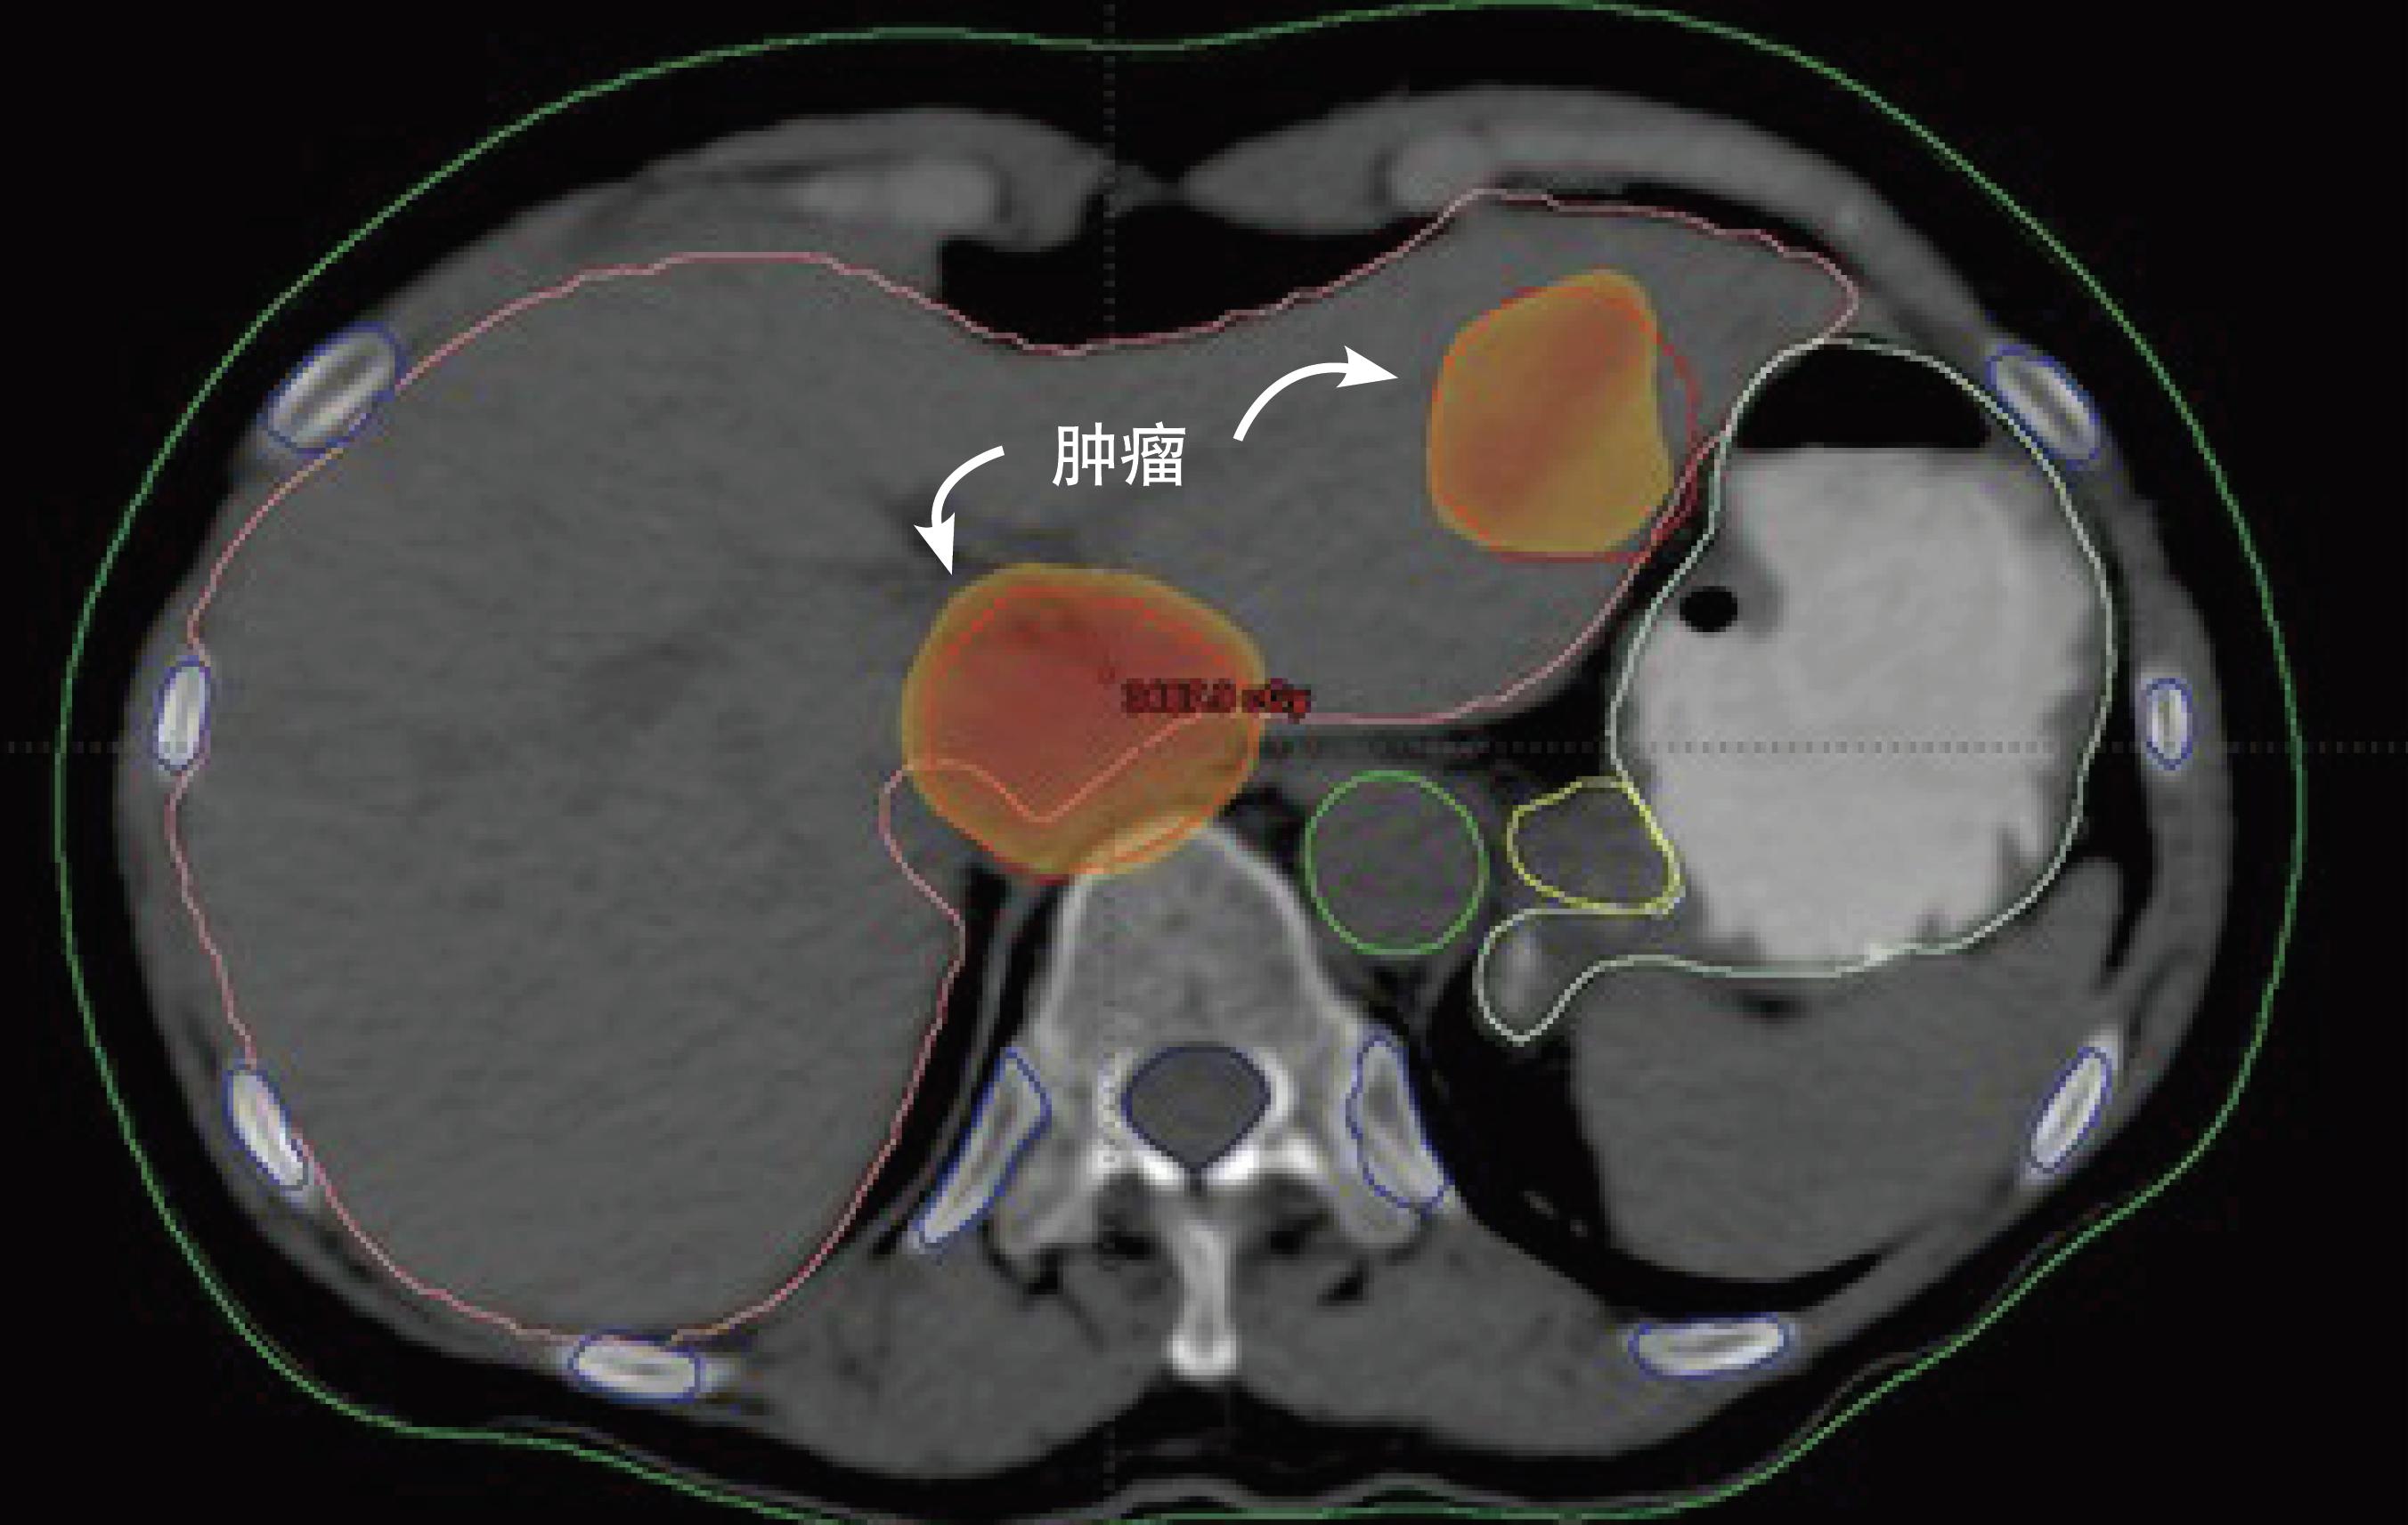

经过简单的问诊,医生清楚了她的症状: 阴道深处触痛、出血。 在检查室,医生发现他的子宫中长了一个肿块,疼痛和出血就是来源于此。

然而,在手术之前, 在并未告知患者的情况下,医生先用手术刀在拉克斯的肿瘤块上,切下了两小片组织,并保存了下来。

但很快,特林德就发现了一个让他和他的研究团队欣喜若狂的事实: 这份来自海瑞塔·拉克斯的“海拉细胞”,在培养皿这种简单的培养环境中,竟然每天都大量增殖,很快就布满了整个培养皿。

而事实上也确实如此, 六十年后,当初的那小小一片肿瘤标本,早已增殖出了超5000万吨“海拉细胞”,至少6万多篇医学肿瘤论文是基于对它的研究。